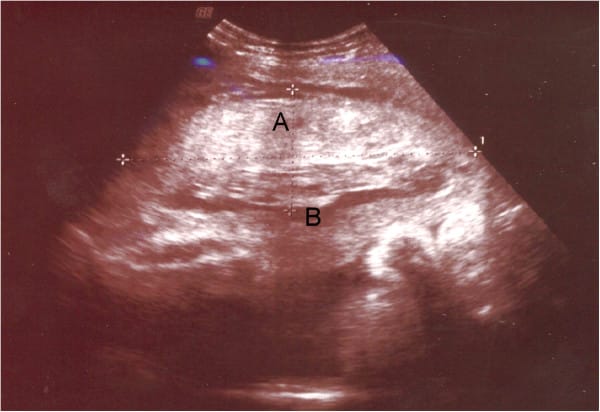

Placental Abruption - Podcast Version TeachMeObGyn 0:00 / 0:00 1x 0.25x 0.5x 0.75x 1x 1.25x 1.5x 1.75x 2x Placental abruption is where a part or all of the placenta separates from the wall of the uterus prematurely. It is an important cause of antepartum haemorrhage – vaginal bleeding from week 24 of gestation until delivery. In this article, we shall look at the pathophysiology, clinical features and management of placental abruption. Pathophysiology Placental abruption is where a part or all of the placenta separates from the wall of the uterus prematurely. Abruption is thought to occur following a rupture of the maternal vessels within the basal layer of the endometrium. Blood accumulates and splits the placental attachment from the basal layer. The detached portion of the placenta is unable to function, leading to rapid fetal compromise. There are two main types of placental abruption: Revealed – bleeding tracks down from the site of placental separation and drains through the cervix. This results in vaginal bleeding. Concealed – the bleeding remains within the uterus, and typically forms a clot retroplacentally. This bleeding is not visible, but can be severe enough to cause systemic shock. Adapted from work by Blausen.com staff [CC BY 3.0], via Wikimedia Commons Fig 1The two main types of placental abruption; concealed and revealed. Risk Factors The major risk factors for placental abruption include: Placental abruption in previous pregnancy (most predictive factor) Pre-eclampsia and other hypertensive disorders Abnormal lie of the baby e.g. transverse Polyhydramnios Abdominal trauma Smoking or drug use e.g. cocaine Bleeding in the first trimester, particularly if a haematoma is seen inside the uterus on a first trimester scan. Underlying thrombophilias Multiple pregnancy Clinical Features Any woman presenting with antepartum haemorrhage should be assessed in a systematic manner (see box below). Placental abruption typically presents with painful vaginal bleeding (bleeding may not be visible if it is concealed). If the woman is in labour, inquire about pain between contractions. On examination, the uterus may be woody (tense all of the time) and painful on palpation. Assessment of Antepartum Haemorrhage History The following questions are useful to ask in the assessment of antepartum haemorrhage: How much bleeding was there and when did is start? Was it fresh red or old brown blood, or was it mixed with mucus? Could the waters have broken (membranes ruptured?) Was it provoked (post-coital) or not? Is there any abdominal pain? Are the fetal movements normal? Are there any risk factors for abruption? e.g. smoking/drug use/trauma – domestic violence is an important cause. If the bleed is ongoing, or if there has been a significant vaginal bleed, ABC assessment and resuscitation is vital. If the woman is clinically stable, proceed to examination. General Examination On general examination, the following should be assessed: Pallor, distress, check capillary refill, are peripheries cool? Is the abdomen tender? Does the uterus feel ‘woody’ or ‘tense’ (which may indicate placental abruption)? Are there palpable contractions? Check the lie and presentation of the fetus/fetuses. Ultrasound can be used to help. Check fetal wellbeing with a cardiotocograph (CTG) at 26 weeks gestation or above: (otherwise auscultate the fetal heart only). Read the hand-held pregnancy notes: are there scan reports? This will be helpful in establishing whether there could be placenta praevia Assessment of Bleeding Lastly, the bleeding itself should be assessed: Externally e.g. by looking at pads. Cusco speculum examination: avoid this until placenta praevia has been excluded by USS. Look for whether blood is fresh red or dark. How much blood is there? Are there clots? Are there any cervical lesions? Is there any cervical dilatation, or any chance that the membranes have ruptured? Take triple genital swabs to exclude infection if the bleeding is minimal Digital vaginal examination: A digital vaginal examination with known placenta praevia should NOT be performed as it could cause massive bleeding. In minor bleed, when placenta praevia is excluded, it can help to establish whether the cervix is beginning to dilate. Avoid digital VE if the membranes have ruptured. Differential Diagnoses Placental abruption is an important cause of antenatal haemorrhage; but it is not the most common. Differential diagnoses to consider include: Placenta praevia – where the placenta is fully or partially attached to the lower uterine segment. Marginal placental bleed – small, partial abruption of the placenta which is large enough to cause revealed bleeding, but not large enough to cause maternal or fetal compromise. Vasa praevia – where fetal blood vessels run near the internal cervical os. It is characterised by a triad of (i) Vaginal bleeding; (ii) Rupture of membranes; and (iii) Fetal compromise. The bleeding occurs following membrane rupture when there is rupture of the umbilical cord vessels, leading to loss of fetal blood and rapid deterioration in fetal condition. Uterine rupture – a full-thickness disruption of the uterine muscle and overlying serosa. This usually occurs in labour with a history of previous caesarean section or previous uterine surgery such as myomectomy. Local genital causes: Benign or malignant lesions – e.g. polyps, carcinoma. cervical ectropion (common). Infections – e.g. candida, bacterial vaginosis and chlamydia. By Gynpath.ru [CC BY-SA 4.0], via Wikimedia Commons Fig 2Cervical ectropion on speculum examination. This is a common cause of antepartum haemorrhage. Investigations If major bleeding is suspected, resuscitate and perform investigations simultaneously. Haematology Full blood count – assess any maternal anaemia. Clotting profile Kleihauer test – if the woman is Rhesus negative (to determine the amount of feto-maternal haemorrhage and thus the dose of Anti-D required). Group and Save – if blood group is unknown. Cross-match – if the clinical presentation is likely to warrant transfusion. Biochemistry These are performed to exclude hypertensive disorders including pre-eclampsia and HELLP syndrome, and any other organ dysfunction: Urea and electrolytes Liver function tests Assess Fetal Wellbeing In women above 26 weeks gestation, a cardiotocograph (CTG) should be performed to assess fetal wellbeing. Imaging An ultrasound scan should be performed when patient is stable. In placental abruption, a retroplacental haematoma may be visible. Ultrasound has a good positive predictive value, but a poor negative predictive value – and should not be used to exclude abruption. Honda et al.; licensee BioMed Central. 2014 [CC BY 4.0] Fig 3Placental abruption on ultrasound. A – retroplacental haematoma. B – placenta. Management Any woman presenting with a significant antepartum haemorrhage should be resuscitated using an ABCDE approach. Do not delay maternal resuscitation in order to determine fetal viability. The ongoing management of placental abruption is dependent on the health of the fetus: Emergency delivery – indicated in the presence of maternal and/or fetal compromise and usually this is by caesarean section unless spontaneous delivery is imminent or operative vaginal birth is achievable. Even if an in-utero fetal death has been diagnosed, a caesarean section may still be indicated if there is maternal compromise. Induction of labour – for haemorrhage at term without maternal or fetal compromise, induction of labour is usually recommended to avoid further bleeding. Conservative management – for some partial or marginal abruptions not associated with maternal or fetal compromise (dependant on the gestation and amount of bleeding). In all cases, give anti-D within 72 hours of the onset of bleeding if the woman is rhesus D negative. Rate This Article